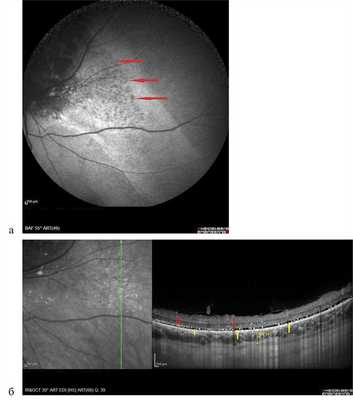

Аутофлюоресценция исследована у 6 пациентов с ГХ, опухоль была представлена участком обширной гипоаутофлюоресценции различной интенсивности (рис. 8, а), в то время как по ФАГ ей соответствовали зоны гиперфлюоресценции собственных сосудов опухоли и сосудистых лакун (см. рис. 8, б). Локальный фиброз, гиперплазия и атрофия пигментного эпителия также представлены зонами гипоаутофлюоресценции. Участки гипераутофлюоресценции соответствовали зонам скопления липофусцина в виде пятен оранжевого пигмента, описанного J. Gass в 1974 г. Вокруг самого узла опухоли в 2 случаях наблюдали обширные зоны умеренной гипераутофлюоресценции за счет наличия свежей субретинальной жидкости с повреждением фоторецепторного слоя и/или альтерацией РПЭ, выявленными по данным ОКТ, точечные участки гипоаутофлюоресценции в этих зонах, по данным ОКТ, соответствовали участкам атрофии РПЭ (рис. 9).

Рис. 8. Картина А.Ф. (а) и ФАГ (б) глазного дна при гемангиоме хориоидеи (объяснения в тексте).

Рис. 9. Картина А.Ф. при гемангиоме хориоидеи и соответствующие данные ОКТ. Вертикальный срез через зону умеренной гипераутофлюоресценции, разрыв слоя фоторецепторов (указан желтыми стрелками, точечный блок АФ в зоне точечной атрофии пигментного эпителия указан красными стрелками).